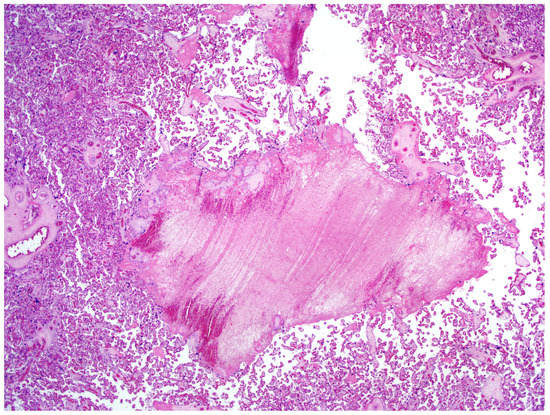

The definitive histological analysis of the placenta did not describe substantial macroscopic alterations, except for mild subchorionic deposition of fibrin and for the presence of a single ischemic area in the thickness of the chorionic disc (0.8 cm of maximum diameter). The amniochorial membranes were smooth and characterized by only focal hemorrhages. The three vessels constituting the umbilical cord was slightly hyperspiralized. Microscopically, neither inflammation of membranes nor funisitis were present. The villous tree showed signs of delayed maturation. The terminal villi were characterized by capillary congestion and focal microchorangiosis. Finally, moderate deposition of fibrin, appearance of villous agglutination, and multiple organizing intervillous hemorrhages were also observed (Figure 2). No substantial differences were found in the proximity of the placental sites, in which the placental swabs were performed.

The histological examination seems to evidence placental alterations which may be caused by an inflammatory status. In fact, a dedicated pathological team described the presence of intervillous hemorrhage. Indeed, several causes may determine fetal capillary rupture, finally determining variable-sized intervillous hemorrhages and a close contact between maternal and fetal blood [22]. At microscopic analysis, moderate fibrin deposition was observed, even considering that the mother was asymptomatic and had an optimal peripheral capillary oxygen saturation. All these pathological findings together with considering the positive qPCR in placental samples and the maternal positive IgG for SARS-CoV2 cannot exclude the hypothesis that COVID-19 can have short- and middle-term physiopathological consequences on placental issue. To support our consideration, in a previous study, the placental examination of pregnant women affected by severe acute respiratory syndrome (SARS) showed an increased amount of subchorionic fibrin deposition, probably secondary to maternal hypoxia [23]. Recently, a USA retrospective analysis evaluated 32 pregnant patients with COVID-19 who delivered; in 11 of them, placental or membrane swabs were performed. Three swabs returned positive results for SARS-CoV-2; notably, all women had severe to critical COVID-19 infection at time of delivery. None of the infants tested had positive swabs for SARS-CoV-2 on days 1 to 5 of life, and none demonstrated symptoms of COVID-19. Given the mixing of maternal and fetal fluid and tissues at the time of delivery, the authors underscored how the detected SARS-CoV-2 RNA may have an unclear origin [24]. In another Italian case series, SARS-CoV-2 RNA was found on the fetal side of the placenta in two cases of mothers infected by COVID-19 and with neonates also positive for the virus at birth. The placentas of these two women who delivered neonates with SARS-CoV-2-positive rhino-pharyngeal swabs showed chronic intervillositis, with presence of macrophages, both in the intervillous and villous spaces [25]. Different from our study, SARS-CoV-2 was detected on placental tissue also using an RNA in situ hybridization (ISH), which enabled the detection of the SARS-CoV-2 spike protein mRNA using a V-nCoV2019-S probe [26]. In this small series, the RNAscope probe detected positive staining for COVID-19 viral RNA in the infected tissues but not in the uninfected placentas [25]. A case of miscarriage during the second trimester of pregnancy in a woman with COVID-19 appeared to be related to placental infection with SARS-CoV-2 and was supported by virologic findings in the placenta. A placental swab was positive for SARS-CoV-2, and at histology, mixed inflammatory infiltrates composed of neutrophils and monocytes in the sub chorial space, intervillous fibrin deposition, and funisitis were demonstrated [27].

Figure 2. Placenta at microscopy. Hematoxylin–eosin (magnification 20×). Organizing intervillous hemorrhage can be visualized.